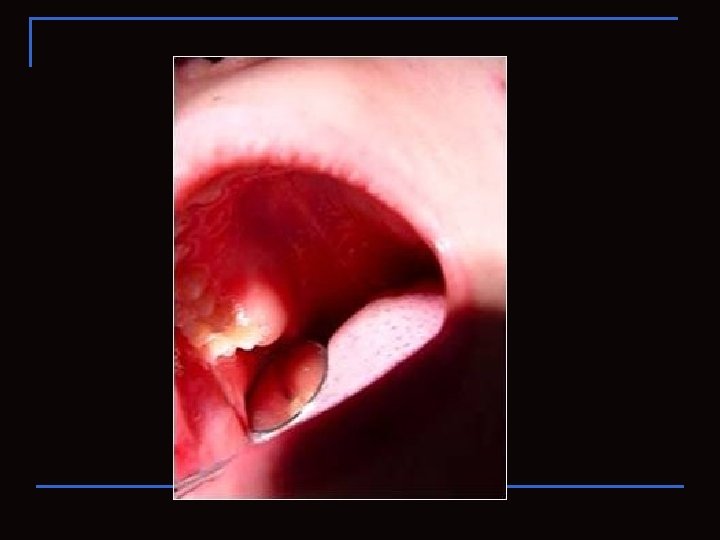

Observen !!!!!